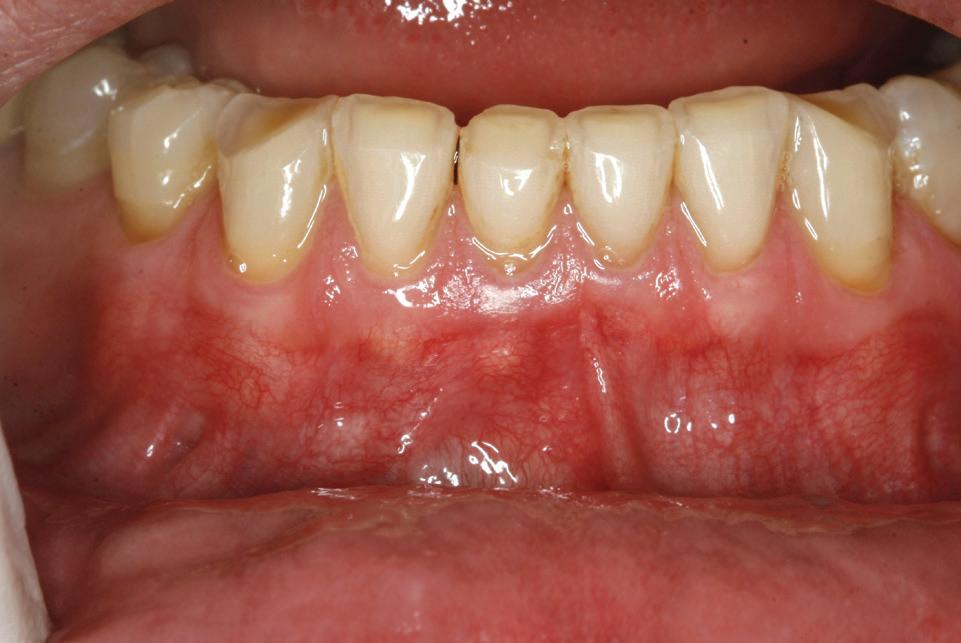

Un pacient caucazian în vârstă de 77 ani s-a prezentat la clinica autorului după cinci ani în care nu a fost la niciun control stomatologic. Examinarea clinică a arătat o pierdere semnificativă de os, parodontită cronică și multiple edentații care au destabilizat ocluzia. Pacientul a raportat sensibilitate la rece la nivelul primului molar drept inferior nr. 46, în special la ingerarea de lichide reci. Radiografia periapicală a confirmat constatările examenului clinic; în

plus, s-a detectat și prezența unei carii radiculare la nivelul rădăcinii distale a aceluiași molar, cu răspuns pozitiv la testul de sensibilitate (fig. 1-2).

Planul de tratament a început cu accent pe restabilirea sănătății parodontale. Într-o ședință ulterioară, odată cu îmbunătățirea stării parodonțiului, s-a efectuat restaurarea molarului nr. 46. Sub anestezie la Spina Spix pe partea dreaptă și

1. Situația clinică inițială.